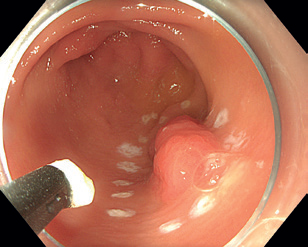

Obr. 4 Stopka polypu po endoskopické polypektomii v bílém světle.Endoskopická slizniční resekce (EMR) je specializovanou technikou pro odstranění povrchových gastrointestinálních lézí, vyvinutou v 50. letech pro sigmoideoskopii a později rozšířenou na kolonoskopii, a nakonec na celý trávicí trakt. Zejména u plochých lézí je výhodné označení okrajů koagulačními body k zajištění odstranění celé léze. Využívá se zejména pro léze větší než 10 mm, které nejsou vhodné pro klasickou polypektomii. Principem EMR je vytvoření pseudopolypu z nepolypoidní léze, což umožňuje lézi zachytit a odstranit pomocí polypektomické kličky.